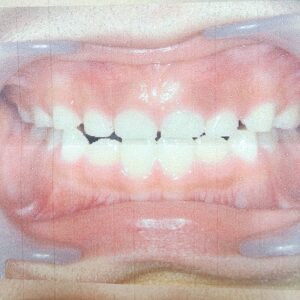

おぺりちゃんは小学校受験が終わった年長さんの冬頃に切端咬合との診断。

反対咬合下の歯が上の歯より前に出てしまう。

切端咬合はその手前。上の歯と下の歯の噛み合わせが浅く前歯で合ってしまう。

と言う歯医者さんでの診断でした。

6歳 切端咬合診断時の写真です。写真をさらに携帯で撮ったので画像が粗くてすいません。

確かに噛み合わせが浅く口を閉じた時前歯と下の歯で噛み合わさってしまっている感じですね。

私から見てもおぺりちゃんはやはり下顎を少し前に出す癖があり、笑ったりすると少しシャクれる感じがありました。